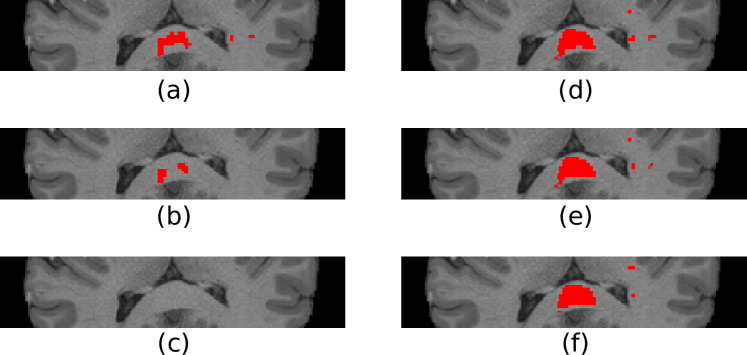

As a proof of concept, results from a single HCP subject performing a motor task are presented; see Figure 4. A substantially greater extent of activations was detected in the corpus callosum from fMRI data filtered using the proposed approach than from data filtered with isotropic Gaussian smoothing. Similarly to the results obtained on phantoms, the detection performance for isotropic Gaussian filtering deteriorates with increasing filter sizes as a result of the increased ratio of extraneous signal mixed with the signal of interest. In contrast, the proposed filters show more homogeneous performance across filter sizes, as they consistently adapt to the shape of the underlying signal.

Refer to caption

Fig. 4: Single subject activations in the corpus callosum from a left hand motor task using: (a)-(c) isotropic Gaussian filtering, FWHM=2FWHM2\text{FWHM}=2mm, 444mm and 666mm respectively. (d)-(e) graph filtering, τ=1.4𝜏1.4\tau=1.4, 2.22.22.2 and 3.33.33.3 respectively. All t-maps thresholded at 5% FDR.